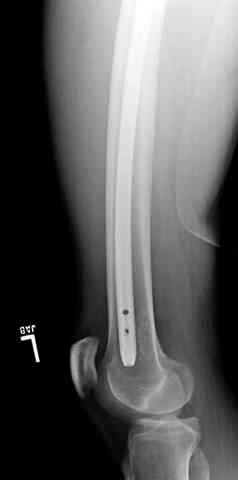

Здесь представлены несколько случаев лечения огнестрельного перелома

1 Проксимальный перелом бедра, антеградный гвоздь

2 внутрисуставной перелом дистального бедра с удалением пули

3 сегментарный перелом бедра с переломом Хоффа фрагментом, сделано из минимального доступа